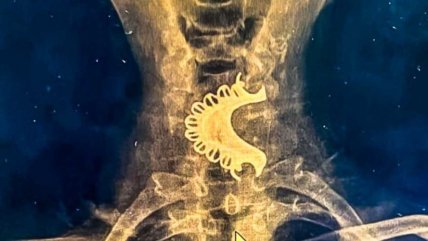

Las cinco etapas del cerebro humano: estudio revela cambios clave a los 9, 32, 66 y 83 años